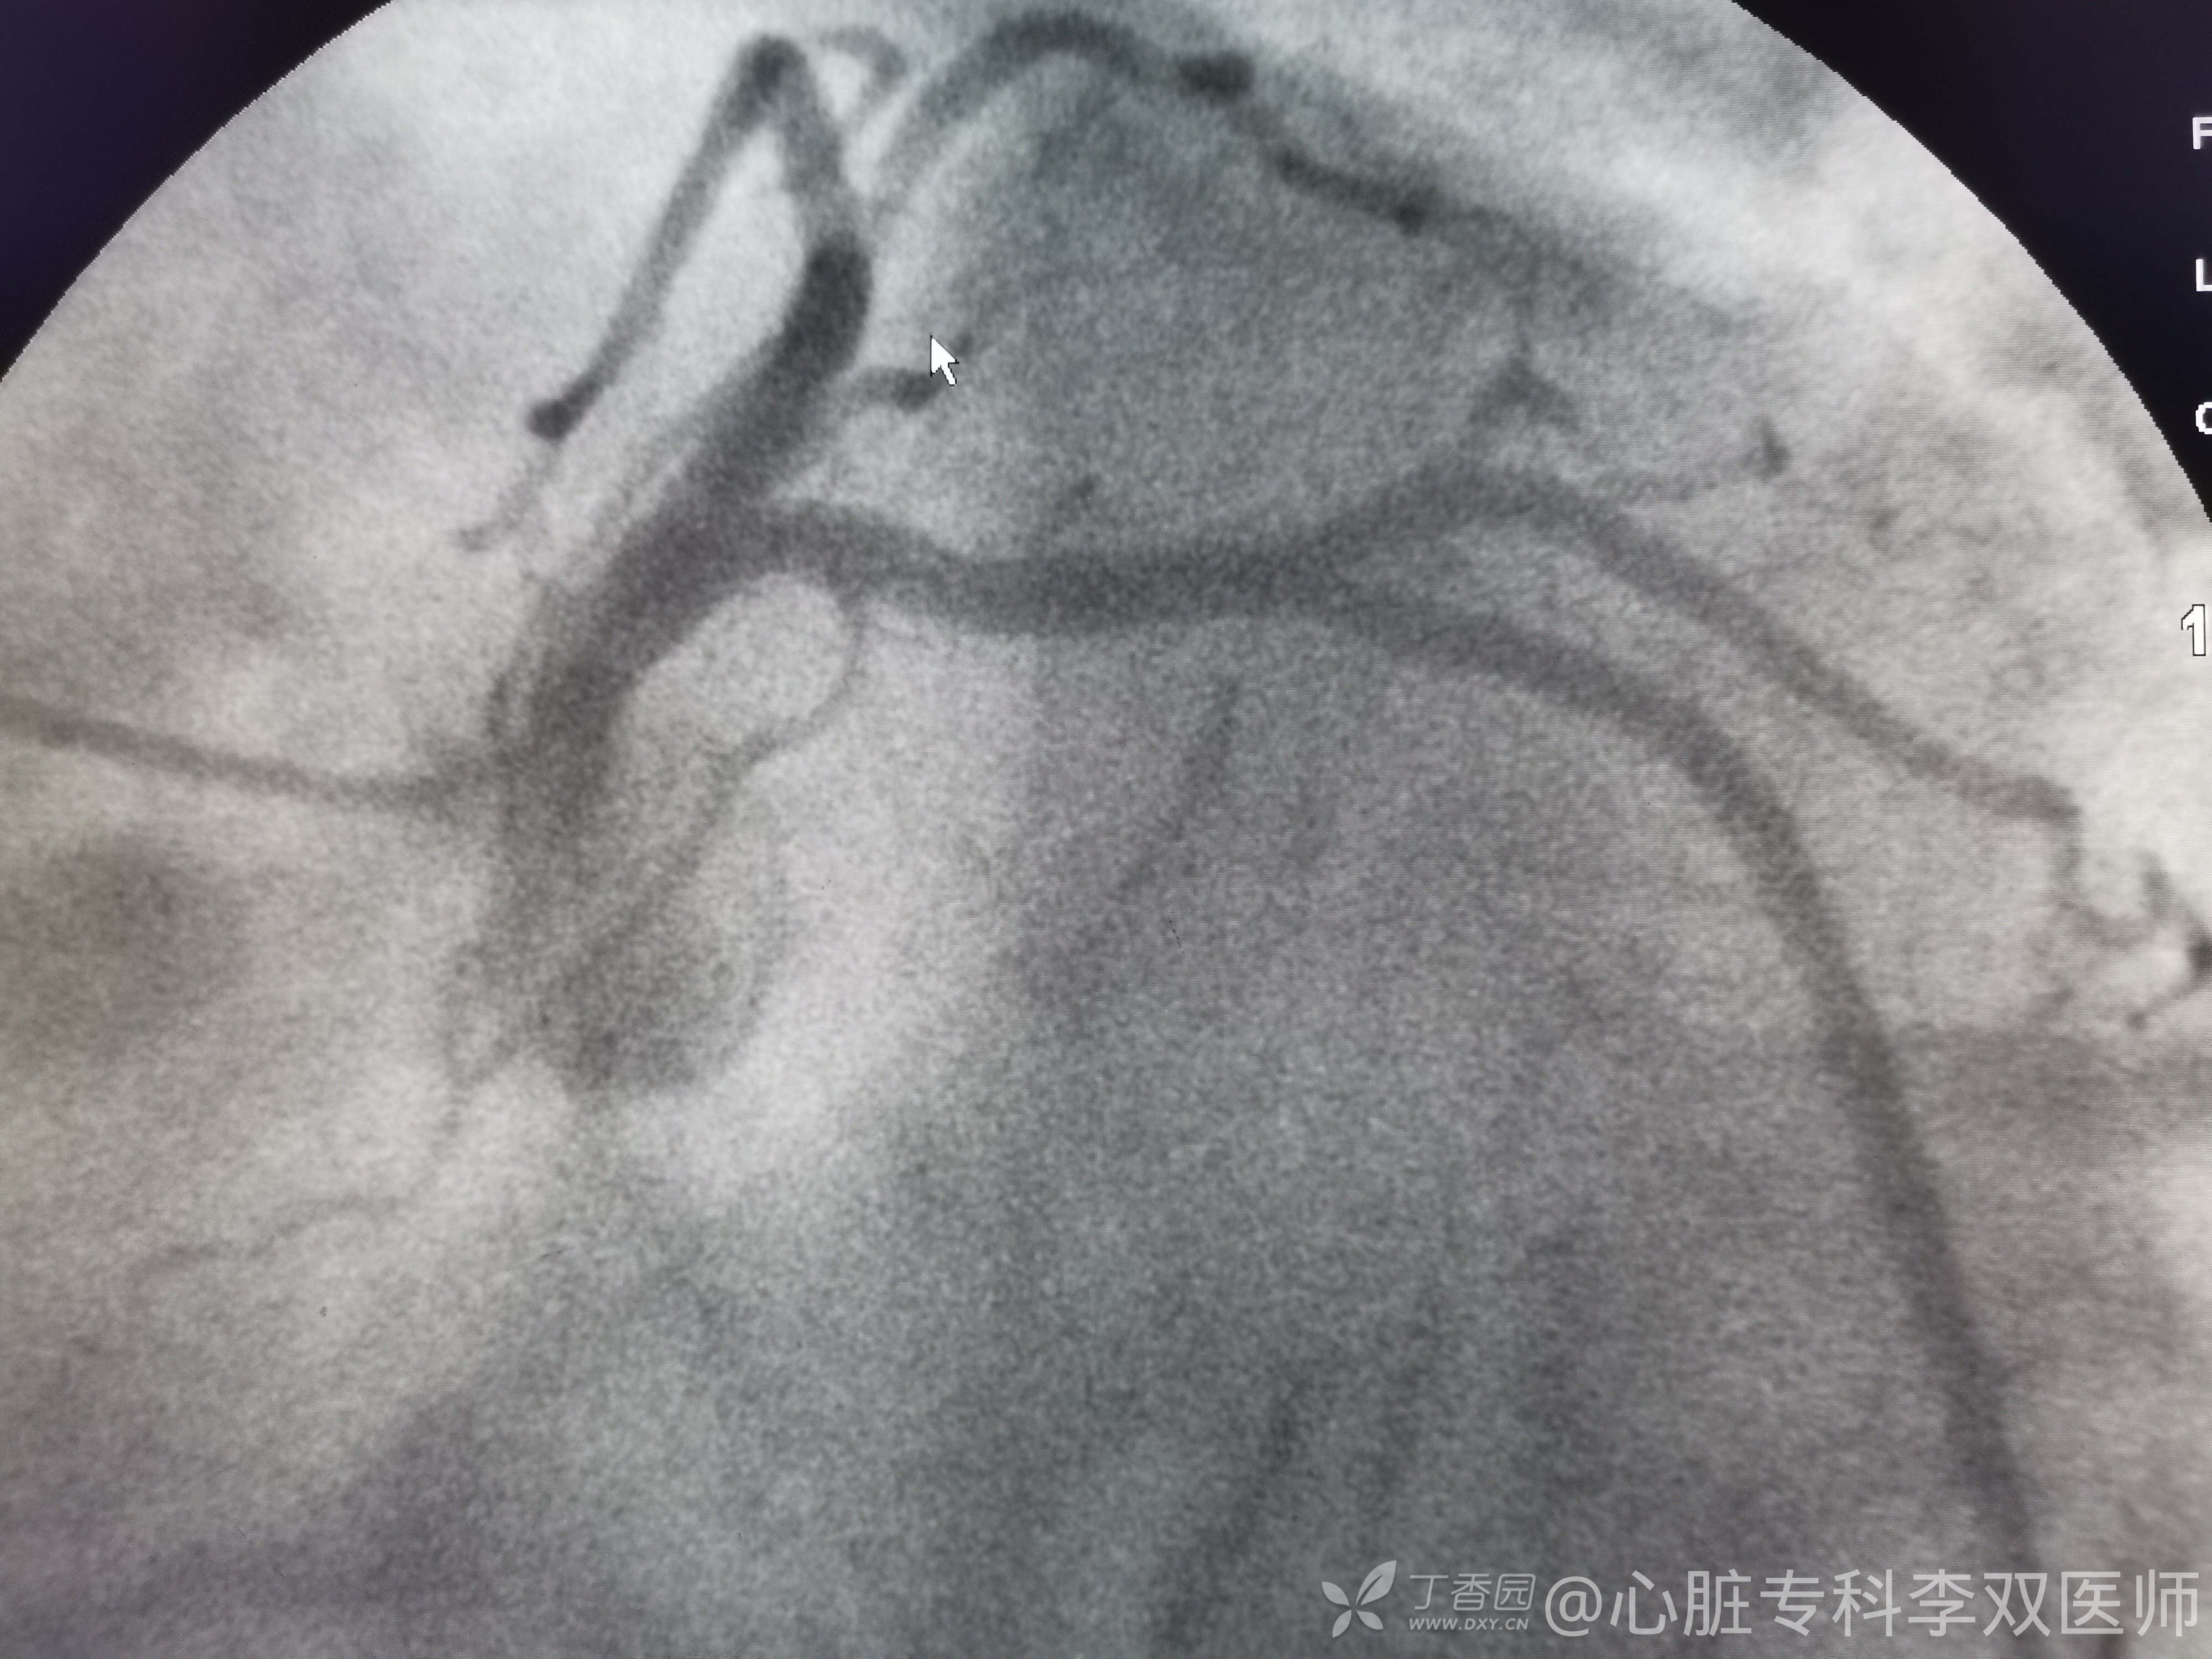

我们会诊考虑确实不能排除心梗,当时做了急诊冠脉造影,不是心梗!(彩超没有报室壁瘤,不过它也排除了血栓,所以才敢打心室造影的)。

心尖部大室壁瘤引起的前壁和侧壁ST抬高,推测患者20年前放支架是急性前壁心梗。